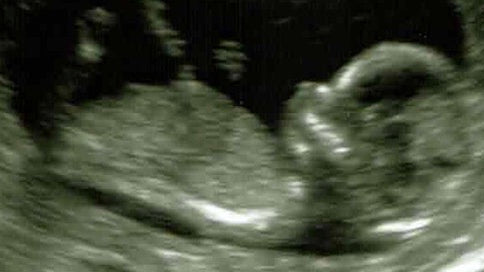

Racing Pregnant & Qualifying for Millrose

Have you ever stepped on the line of a race and were terrified you wouldn’t have what it takes to achieve what you wanted, what you desired, what you needed? I’m not talking about nerves, fear of competition, or even self-doubt. I’m talking about actual physical limitation.